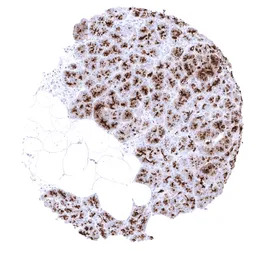

IHC-P analysis of human pancreas tissue section using GTX04397 MUC1 antibody [MSVA-672R] HistoMAX.

Pancreatic acinar cells show a strong MUC1 immunostaining of the apical membranes and of granular Golgi like structures below the apical surface.